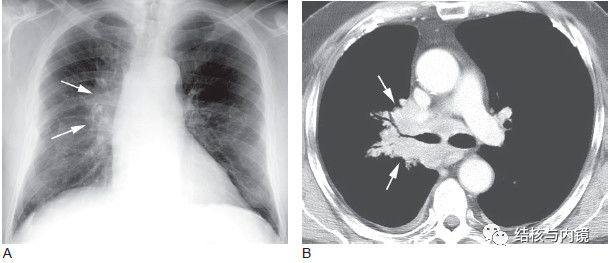

支气管镜诊断结核性肺门纵隔淋巴结炎TBLA

仅有肺门纵隔淋巴结肿大而无肺实质受累时,痰结核菌涂片和培养阳性率均极低,尽管通过纵隔

经支气管镜针吸活检术TBNA是应用一种特制的穿刺针,通过支气管镜活检孔对气管支气管腔外病变获取细胞或组织标本进行细胞病理学及组织学/细菌学诊断的一种新技术。

细胞病理学联合结核分枝杆菌培养提高了TBNA的阳性率